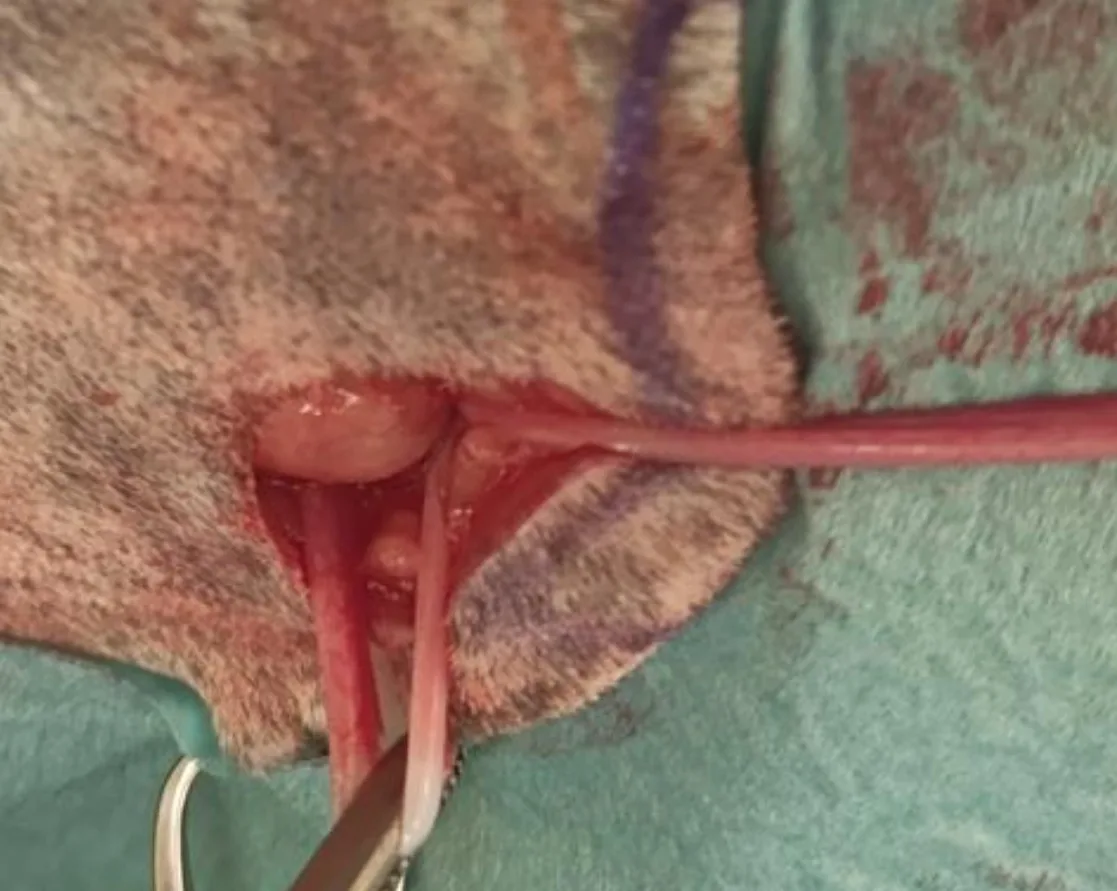

Step 6: Remove the Uterine Horns

Bluntly dissect the broad ligaments to exteriorize the uterine horns, and place 1 straight and 1 curved Halsted mosquito forcep proximally to the cervix. Use 1 encircling ligature and a transfixing ligature in the uterine body, with the uterus transected between the hemostats.

Author Insight

If pronounced development of the broad ligament vasculature is noted, ligation may be necessary.